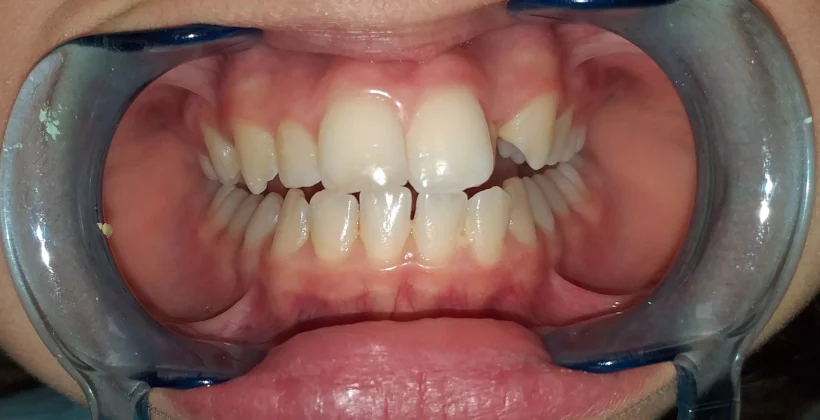

Kezelés előtt

Fiatal, 14 éves páciensemet a felső fogsorának látványos esztétikai problémája zavarta. A bal oldali kismetsző foga a fogváltás után, palatinálisan helyezkedett el, vagyis nem a többi foggal egy vonalban, hanem beljebb a szájpadlás irányába bújt elő, így takarásba került, és olyan hatást keltett, mintha hiányozna egy frontfoga.

Vizsgálat után enyhe mélyharapást, felső fogív szűkületet, a bal felső kismetsző keresztharapását, fogtorlódást és az alsó frontfogak enyhe, helyzeti rendellenességét állapítottam meg.